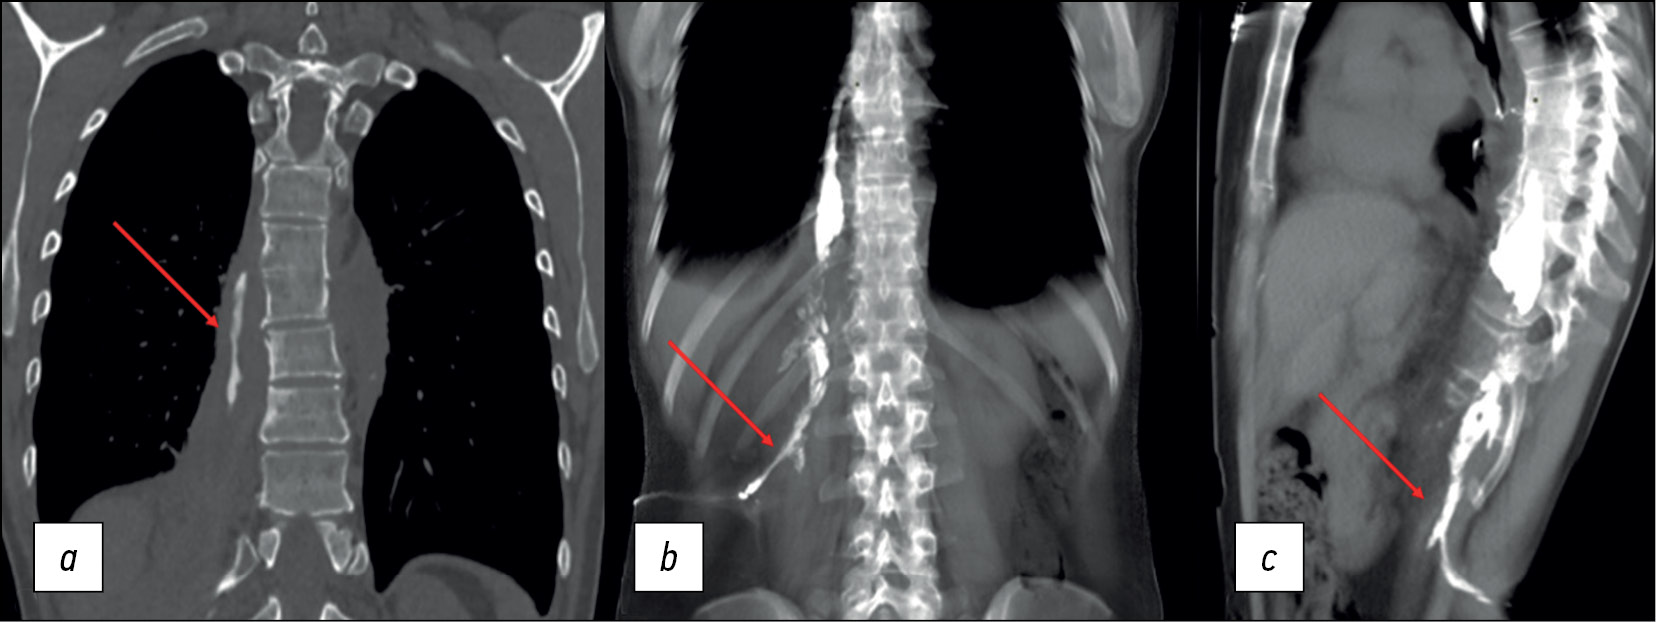

At different outpatient facilities, the patient had surgery (fistulotomy and abscessotomy) three times. The surgical specimen contained hemolytic streptococcus susceptible to amoxiclav, ampicillin, cefotaxime, vancomycin, doxycycline, and meropenem. The patient received targeted antibiotic medication with no effect. Before admission to the St. Petersburg Research Institute of Phthisiopulmonology, a computed tomography (CT) revealed symptoms of prior spondylitis ТhVII–ТhVIII and a right-sided psoas abscess (Figure 2).

Fig. 2. Lumbar spine MRI: (a) soft tissue mode, axial plane, and (b) soft tissue mode, coronal plane. The arrows indicate the right psoas muscle abscess.

During the additional history taking, the patient reported an association between his food intake (mostly liquid food), the onset of pain, and the type of discharge from the lumbar fistula tract. Due to these symptoms, a CT esophagography with oral contrast revealed a fistula tract at the ТhVII level extending from the esophagus to the right paravertebral space up to the ThX level and loculated empyema on the right. An additional CT fistulography was performed to determine the length of the fistula tract, with a contract solution (iopromide 370) injected into the lumbar fistula located on the right at the LIII level. The CT fistulography revealed a fistula tract extending from the right psoas major muscle to the ТhVII level. The fistula tract linked with the esophageal lumen at the same level, where the contrast agent was visible (Figure 3).

Fig. 3. (а) CT esophagography with oral contrast, coronal plane and (b and c) CT fistulography, multiplanar reconstruction (MPR), coronal and sagittal plane. The arrows indicate the fistula tract from the esophagus to the right paravertebral space, from the ТhVII to the ThX level.